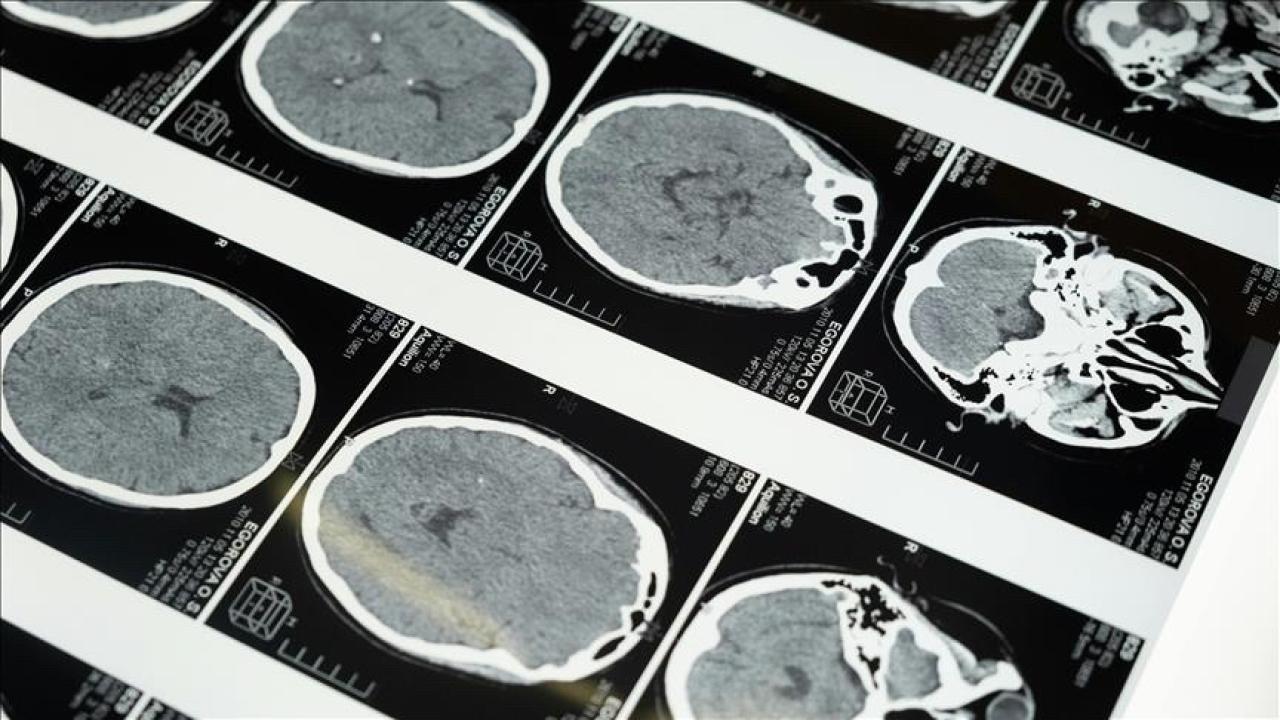

Uzun süre tanı almayan çölyak, beyin yapısını da etkiliyor

Giresun Eğitim ve Araştırma Hastanesi Gastroenteroloji Ana Bilim Dalı tarafından yürütülen bilimsel çalışmalar, uluslararası alanda ses getirdi. Ga...